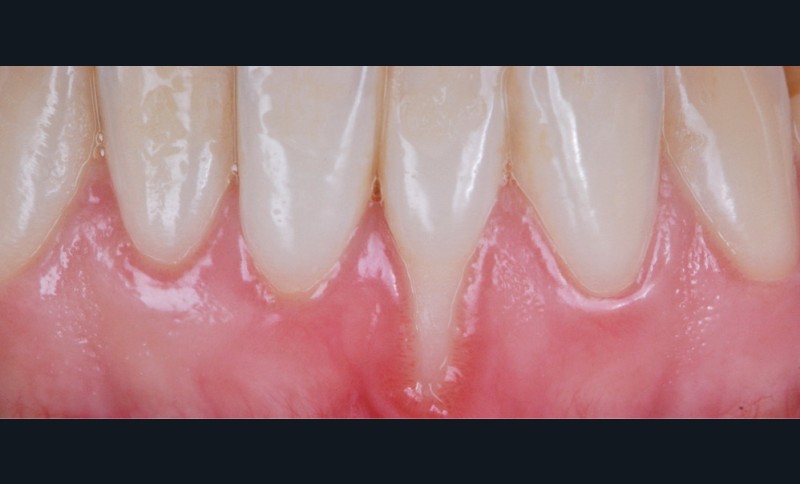

Zuchelli et coll. [1] définissent quatre causes à l’origine des récessions gingivales à la suite d’une déhiscence osseuse : les causes traumatiques (fig. 1) par le brossage, le surcontour prothétique, les piercings ; les causes bactériennes (fig. 2) liées à une inflammation marginale ; les causes virales par le virus de l’herpès simple ; et les origines mixtes, à savoir traumatiques et bactériennes (fig. 3). Le diagnostic de récession liée à la plaque dentaire dépend de la présence de dépôts tartriques et/ou d’inflammation des tissus environnant les zones exposées. En présence d’une origine mixte, la récession est d’abord initiée par un brossage traumatisant, rendant la surface radiculaire hypersensible ou irrégulière, ayant une répercussion négative sur le brossage et l’accessibilité à l’hygiène.